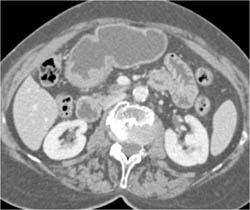

Glomus Tumor